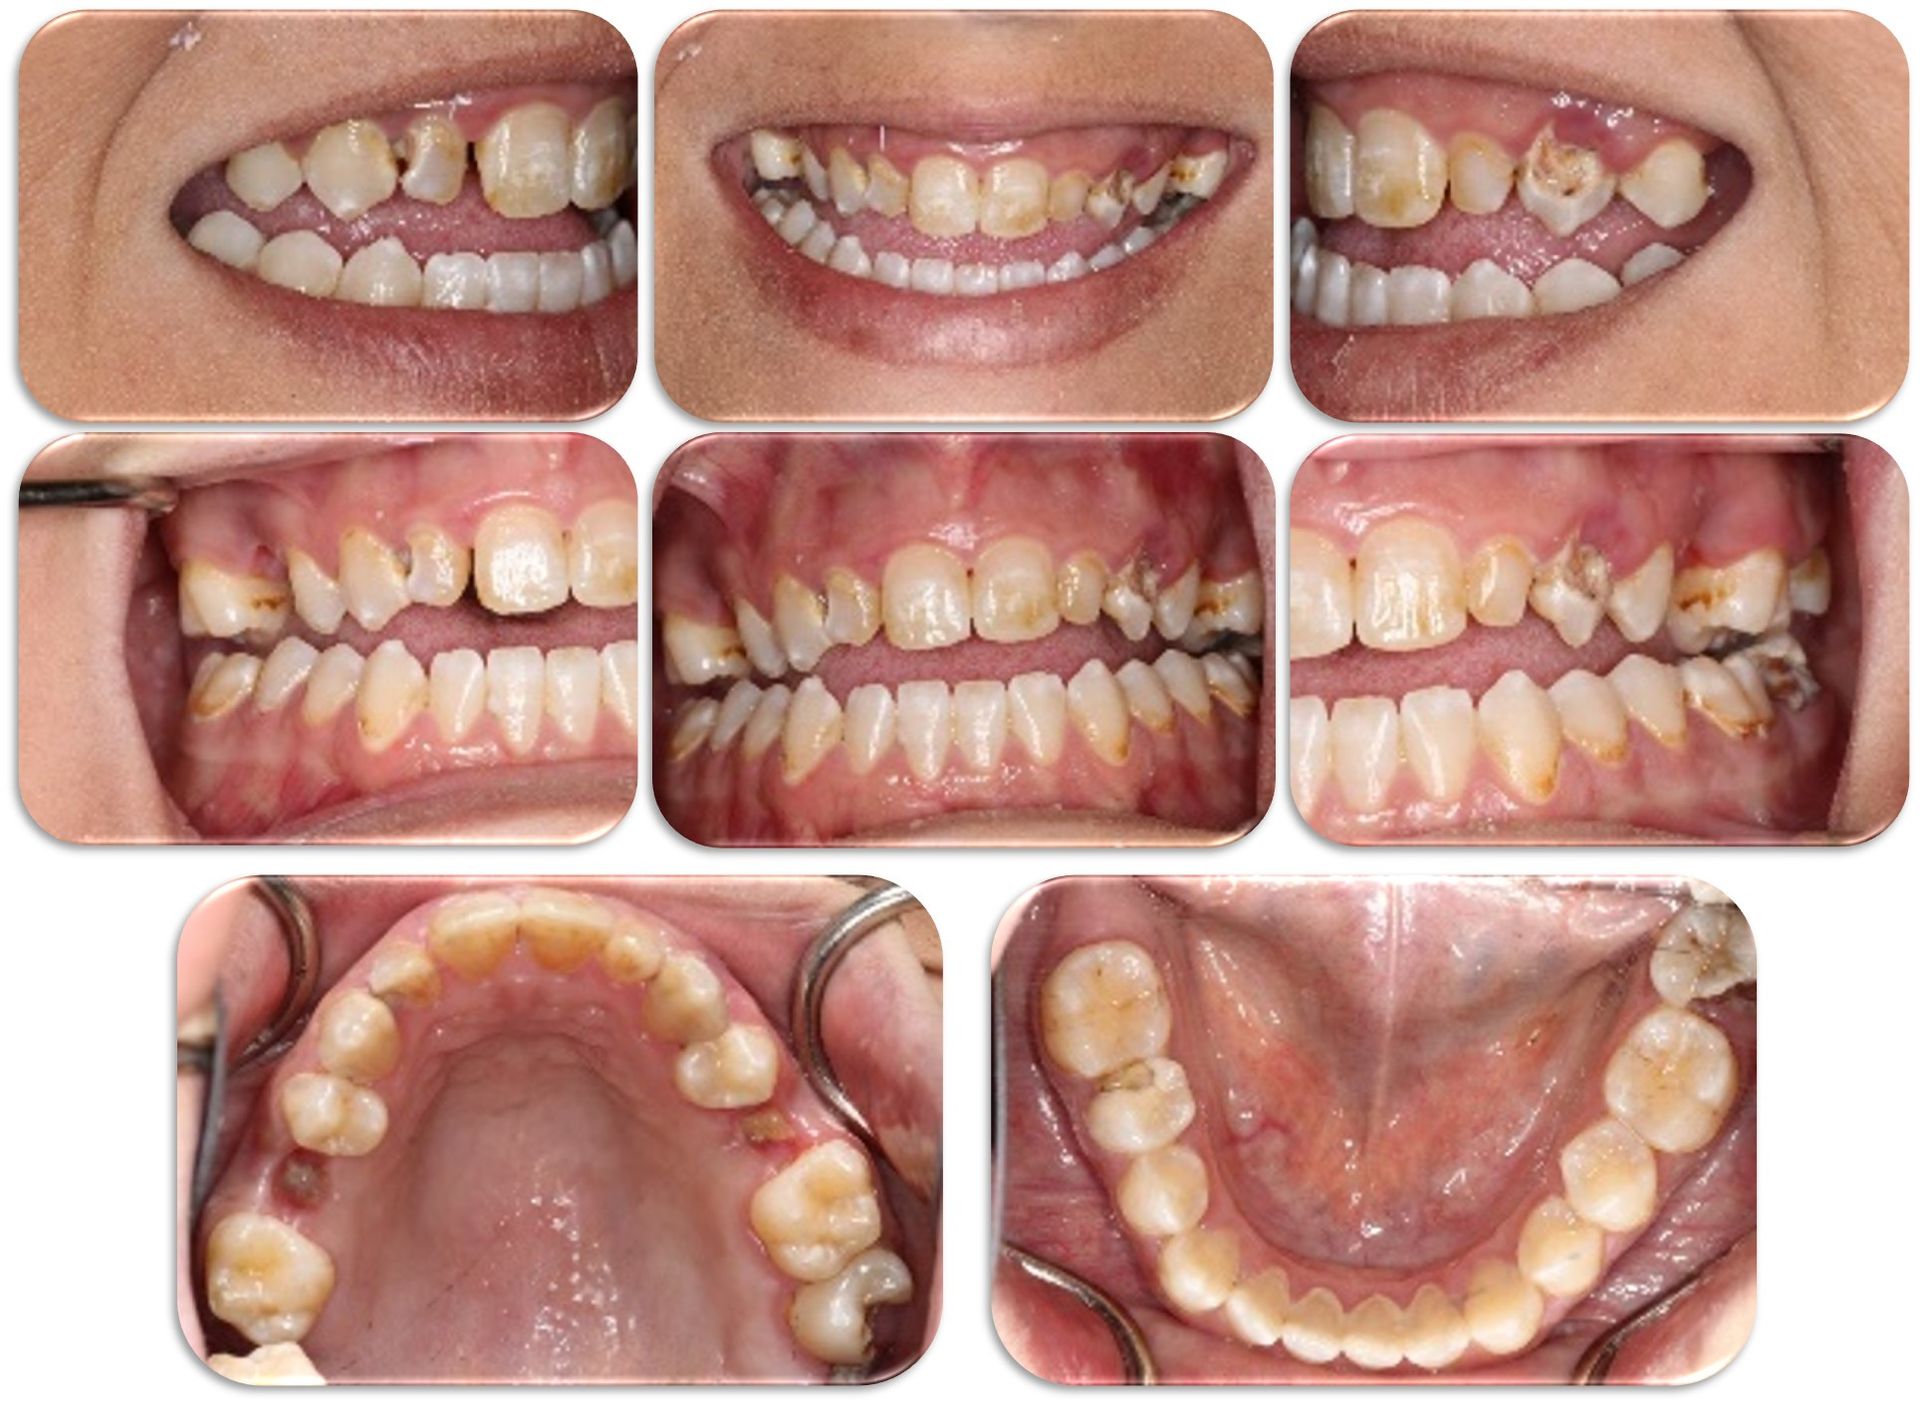

- Photography: Learn and practice the basic photos you need to use for your case presentation

- Learn and practice the basic photos you need to use for your case presentation